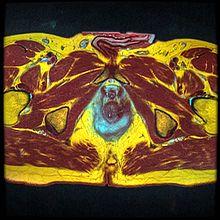

MRI image of U-shaped fluid collection around the anus, showing perianal abscess formation.

Diagnosis of anorectal abscess begins with a medical history and physical exam. Imaging studies which can help determine the diagnosis in cases of a deep non-palpable perirectal abscess include pelvic CT scan, MRI or trans-rectal ultrasound. These studies are not necessary, though, in cases which the diagnosis can be made upon physical exam.